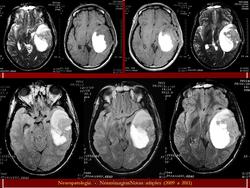

ГМ. Примитивная нейроэктодермальная опухоль (ПНЭО). +

Примитивная нейроэктодермальная опухоль (ПНЭО)